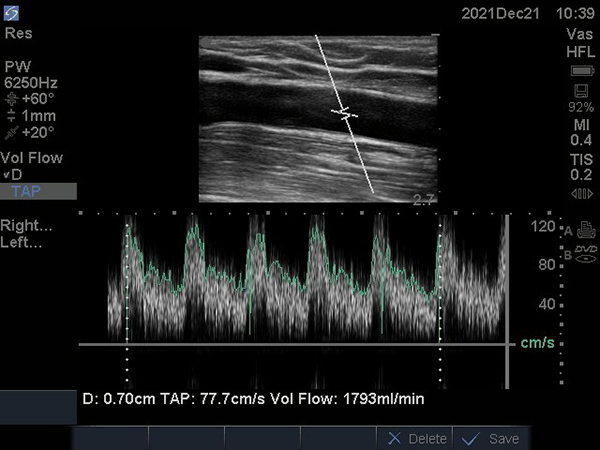

患者李某,男,51歲,規(guī)律血液透析,5年前在徐醫(yī)附院行自體動靜脈內(nèi)瘺(AVF)。近期AVF震顫減弱,流量欠佳,只能達到200ml/min,遂到徐醫(yī)附院就診。術(shù)前超聲檢查示AVF動脈穿刺點上游血管狹窄,長度約4cm,最狹窄處僅有2.5mm,伴吻合口狹窄;颊呓(jīng)過PTA治療,AVF震顫明顯增強,流量達到1793ml/min,完全滿足透析要求,手術(shù)成功。